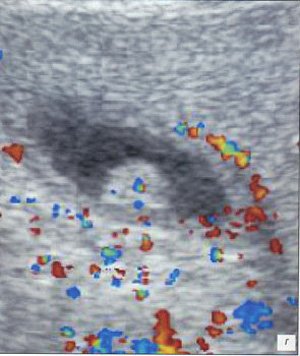

При УЗИ органов брюшной полости в правой подвздошной области и/или несколько выше (паракавально) определялись лимфоузлы с воспалительными изменениями, которые выглядели как единичные или множественные (часто - конгломерат) неправильно-округлой формы образования с ровными, четкими контурами, пониженной эхогенности (рис. 4 а-г). Максимальные размеры лимфоузлов у детей при банальном мезадените достигали 25-28 мм. Обычно в конгломерате имелось 2-3 крупных лимфоузла, к которым прилежали многочисленные более мелкие.

Острое воспаление лимфоузла проявлялось изменением его формы (он становился более округлым) и диффузным понижением эхогенности, при допплеровском исследовании определялась гиперемия лимфоузлов в виде усиления сосудистого рисунка со снижением резистивного индекса артериального кровотока до 0,6 и ниже. По мере стихания остроты воспалительного процесса эхогенность лимфоузлов повышалась, форма становилась уплощенной, лимфоузлы постепенно (недели, иногда - месяцы) уменьшались в размерах и исчезали. Эхографические изменения, расцениваемые как проявления острой воспалительной трансформации лимфоузлов (округлой формы, гипоэхогенные, чаще - более 10-14 мм в диаметре в зависимости от возраста ребенка), клинически проявлялись абдоминальным болевым синдромом, по мере стихания воспалительных изменений (плоские лимфоузлы средней эхогенности) субъективных жалоб дети не предъявляли. В одном случае абдоминальный болевой синдром у ребенка был вызван инородным телом двенадцатиперстной кишки с развитием эрозивного гастродуоденита, мезаденита. Обнаружение инородных тел линейной формы при УЗИ представляет собой большую сложность и возможно только при тщательном полипозиционном сканировании (рис. 4 д-з).

а, б) Исследование в В-режиме и допплеровское сканирование в энергетическом режиме при мезадените. Ребенок, 6 лет. Определяется конгломерат гиперемированных лимфоузлов пониженной эхогенности.